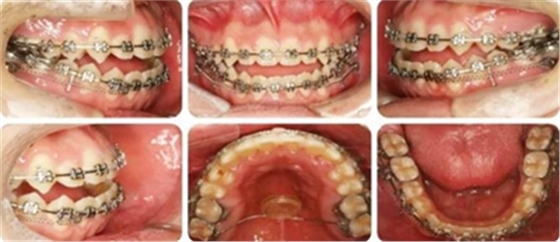

結(jié)束時(shí),可見前牙覆合覆蓋正常,上下牙列排齊,雙側(cè)尖磨牙達(dá)到中性關(guān)系。

高角反頜伴開頜病例,多采用正畸正頜聯(lián)合治療。但該患者為直面型,下牙列輕度擁擠,下前牙直立,且年齡較小,手術(shù)治療非首選。采用種植釘內(nèi)收下前牙代償性治療前牙反合。而且需要拔除阻生智齒減小遠(yuǎn)移下牙列的阻力。

羅晨醫(yī)生:我今天展示的病例,技術(shù)創(chuàng)新在于種植釘整體遠(yuǎn)移下頜全牙列。臨床正畸治療中,對(duì)于反頜伴開頜的患者,一直是令人困擾的難題。以往的上頜骨嚴(yán)重發(fā)育不足的患者,只能通過正頜手術(shù)進(jìn)行改善,但一來患者比較痛苦,二來費(fèi)用較高,

給患者帶來很大的負(fù)擔(dān)。而本病例通過下頜頰棚區(qū)植入微種植釘,整體將下頜牙列內(nèi)收,引起下頜骨逆時(shí)針旋轉(zhuǎn),開合和反合得到了糾正,達(dá)到了良好的效果。